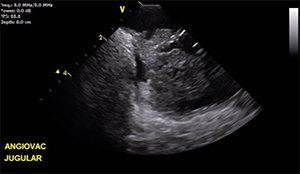

There are three catheter-based thrombus removal devices: the Ekos acoustic pulse thrombolysis system, FlowTriever thrombectomy system, and AngioVac. I have had good results with the Ekos acoustic pulse thrombolysis system for PE. A long infusion lysis catheter (≥ 18 cm) can be left in situ to elute tissue plasminogen activator all the way from the pulmonary artery across the right ventricular outflow tract and right atrium, although this might not be a very effective strategy for right atrial thrombus. The FlowTriever thrombectomy system is a relatively simple device indicated for mechanical pulmonary embolectomy. However, I am not sure how safe it would be to use in the right atrium, given that it is recommended to prevent the catheter end from touching the vessel wall and the right atrium is a very thin structure. The catheter is delivered over the wire but is not steerable. AngioVac is indicated for percutaneous right atrial thrombectomy. One possible approach would be to use the inflow circuit via the internal jugular approach, while the return circuit would be into the femoral vein. The device is also steerable.

In this patient, I would suggest treating the PE first with either a short protocol Ekos or attempt thrombectomy with the FlowTriever. Once the patient is stabilized by reducing the PE burden, right atrial thrombectomy can be performed with the AngioVac device. The compelling reasons for removal of the right atrial clot in this patient is a large paradoxical embolism to the distal aorta via the large intracardiac shunt, and unless this thrombus is removed, the risk for a repeat event still exists.

Drs. Dhamija, Kalra, Kanaa’N: We would elect to immediately use Ekos (catheter-directed thrombolytic therapy) for dissolution of the PE. AngioVac (a suction filtration device) could then be used for aspiration of the right atrial mass as a staged procedure after PFO closure.

Given the active paradoxical embolization, the decision was made to perform PFO closure initially. This was successfully achieved with a 30-mm Cardioform device guided by intracardiac echocardiography without complications. The patient underwent a staged extraction of the right atrial mass with an AngioVac cannula 72 hours later. Pathologic examination of the extracted mass revealed predominantly thrombus without evidence of tumor (Figure 2). I agree with the panelists that a more aggressive approach to the PE could have been taken. However, concerns were raised about the use of tissue plasminogen activator (albeit locally) given the fresh femoral cutdown sites that were used to perform the aortoiliac thrombectomy.